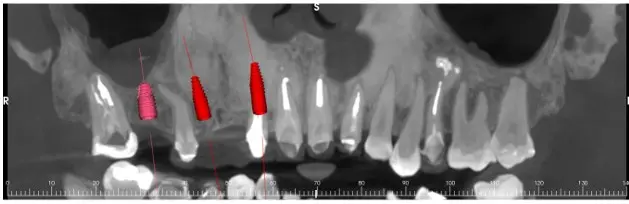

Maxillary Implant Case — 3 Implants

Tooth-supported guide for 3 implants in the upper jaw. Digital planning with precise implant positioning.